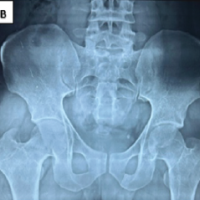

Weight-bearing knee radiographs (anteroposterior and lateral) were obtained to confirm medial compartment OA and grade severity using the KL classification [3]. Full-length, weight-bearing hip-knee-ankle scanograms were acquired with strict attention to limb positioning: Central patella, appropriate visibility of the lesser trochanter, and fibular head overlap ensured accurate axis measurements. We determined the mechanical tibiofemoral angle and joint line convergence angle (JLCA), crucial for planning correction.

Pre-operative planning: Miniaci method

Pre-operative planning utilized the Miniaci technique for the determination of wedge opening in medial open-wedge osteotomy [4]. On weight-bearing scanograms, the planned weight-bearing line (first line) was drawn from the hip center through the desired point on the tibial plateau to the anticipated ankle center. The hinge point was identified on the lateral proximal tibia adjacent to the fibular head. The angle between the line from the ankle center to the hinge point and the line from the hinge point to the anticipated new ankle center represented the required correction angle. When a self-correction component of JLCA was expected, this angle was subtracted from the total planned correction. The resultant angle was converted into a gap size at the osteotomy site using trigonometric reference charts.

Pre-operative correction planning was performed using the Miniaci method, as originally described by Miniaci et al., which enables precise calculation of the required wedge opening by projecting the mechanical weight-bearing axis through the Fujisawa point and determining the hinge-based angular correction. The intended post-operative mechanical axis was targeted to pass approximately 62.5% lateral to the tibial plateau width. In our series, the achieved mean post-operative varus angle was 2.4 ± 0.65°, closely approximating the planned correction and thereby confirming the reliability and reproducibility of the Miniaci technique in achieving accurate alignment. [4,17] Though we did not use bone substitutes or wedges in our series, several authors have reported satisfactory union rates and maintenance of correction with their use in open-wedge high tibial osteotomy. [18]